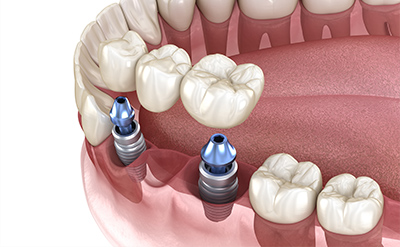

インプラントは単に歯の欠損を補う入れ歯やブリッジとは異なり、失った歯を「根っこからもう一度再生する」ことができる治療法です。顎の骨に人工の歯根をしっかりと固定するため、入れ歯のようにズレたり、周りの健康な歯を削ったりする必要がありません。ご自身の歯とほとんど変わらない感覚でしっかりと噛むことができ、人生をより豊かにしてくれます。

顎の骨に直接埋め込むので、周囲の健康な歯に負担をかけずに治療を行うことができます。隣接する健康な歯を削ったり支えにしたりする必要もなく、失った歯だけをしっかり補うことができます。